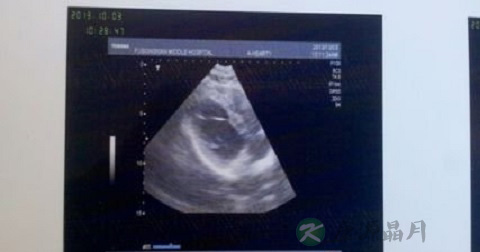

彩超采用的相关技术是脉冲波,对检测物速度过高时,彩流颜色会发生差错,在定量分析方面明显逊色于频谱多普勒,现今彩色多普勒超声仪均具有频谱多普勒的功能,即为彩色──双功能超声。彩色多普勒超声血流图(CDF)又称彩色多普勒超声显像(CDI),它获得的回声信息来源和频谱多普勒一致,血流的分布和方向呈二维显示,不同的速度以不同的颜色加以区别。

彩超检查就是高清晰度的黑白b超,肝病患者通过彩超检查,能从肝内各种血管管腔大小、方向及侧支循环的建立作出很好的判断。对于黑白超难区分的结节性硬化、弥漫性肝癌,可利于高频探查、血流频谱探查作出鉴别诊断。因此,彩超可以查出肝硬化。